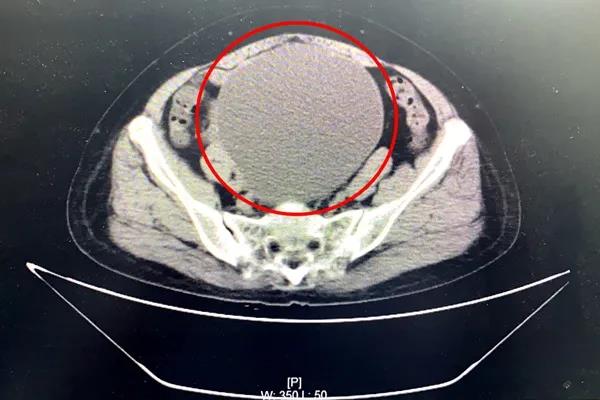

7月13日,63岁的陆阿姨来到我院外科门诊就诊。她自觉6月开始腹部增大明显,并感腹部坠胀不适感。外科检查全腹部CT提示:盆腔内巨大囊性病灶,考虑浆液性囊腺瘤,近20公分大!患者及家属对病情十分担忧。

妇产科顾爱玲主任前来会诊。经检查,患者腹部包块增大明显,盆腔巨大包块已如怀孕近6月大小。顾主任详细问询病史、查体,并再次至放射科与医生共同阅片,考虑患者巨大盆腔肿物瘤良性可能大。她与患者及家属详细沟通了相关病情,逐渐打消了患者及家属顾虑。患者及家属决定留我院进一步诊治。